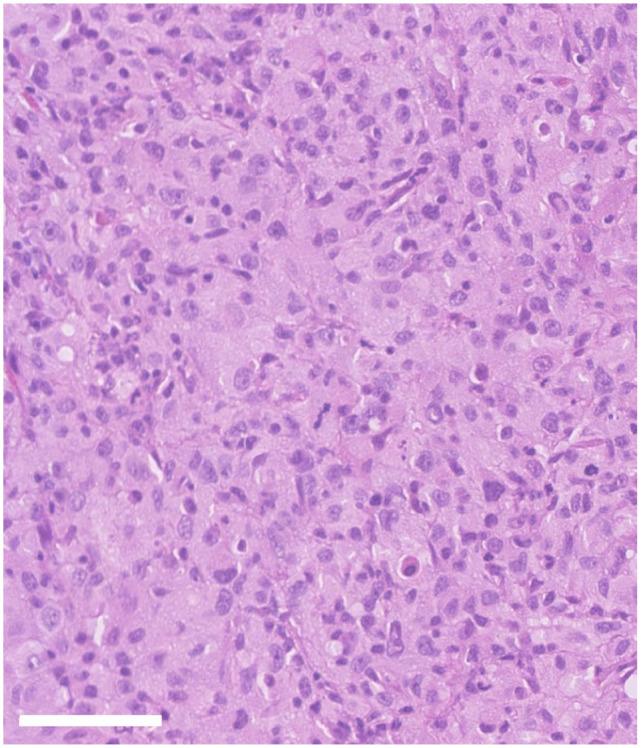

CASE SUMMARY

A 15-year-old neutered male domestic shorthair cat presented with a 4-week history of dysphonia and reluctance to chew hard food. Oral examination revealed a mass lesion on the caudal soft palate. Biopsy was performed and histopathology with immunohistochemistry was most consistent with histiocytic sarcoma. CT of the head identified a discrete, left-sided, soft tissue mass lesion cranial to the tonsil with bilaterally symmetrical regional lymph nodes. CT of the thorax was unremarkable. Surgical removal achieved cytoreduction but not complete removal. Adjuvant chemotherapy with lomustine 10 mg (30 mg/m) was initiated. The patient developed suspected pancreatitis 2-3 weeks postoperatively, so further chemotherapy treatment was discontinued, but supportive treatment with pain relief and appetite stimulants was provided. Three months postoperatively, the patient developed recurrent dysphonia, and oral examination revealed a suspicion of local recurrence. Confirmation of diagnosis (cytopathology or histopathology) was not obtained. Supportive treatment to maintain a good quality of life was continued and the patient was euthanased 6 months after diagnosis owing to progressive disease.

RELEVANCE AND NOVEL INFORMATION

Only a few reports have been published describing histiocytic diseases of cats. To our knowledge, this is the first report of a feline histiocytic sarcoma of the oral cavity. Therefore, histiocytic sarcoma should be considered as a differential diagnosis in feline patients with an oral mass, especially if histopathology suggests a pleomorphic and poorly differentiated sarcoma. Immunohistochemistry for the confirmation of cell line origin would be strongly recommended.